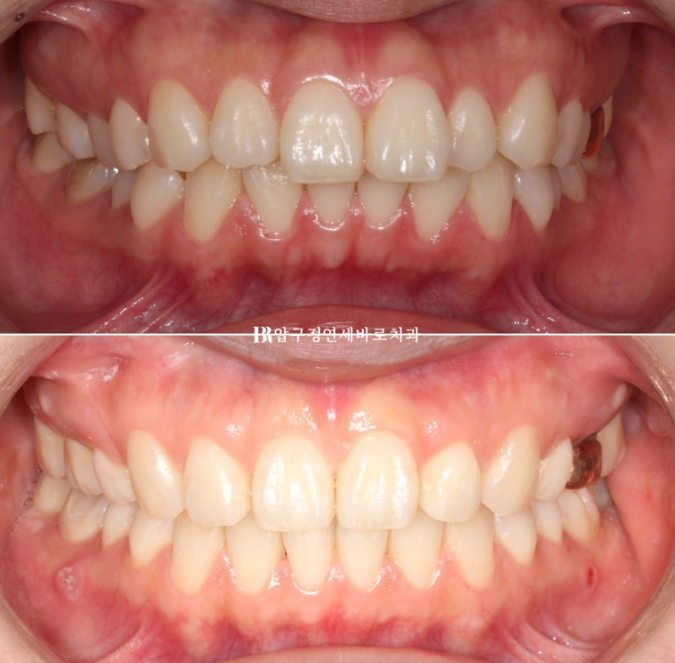

If the upper front teeth protrude severely, the lower lip ends up resting between the upper and lower front teeth, and when the mouth is closed, the upper front teeth show slightly through the lips.

With the protrusion resolved, the lips that could not close comfortably now close easily.

23.06~25.01

Lip incompetence was resolved.

Although this was extraction orthodontics, the fullness of the lips was well preserved.

The gummy smile was also resolved, and the absent buccal corridor was created.

One change that came with the buccal corridor is that the smile changed from a somewhat cramped look, where the gums and teeth seemed tightly packed when smiling, to a smaller and cleaner-looking smile.

The protruding appearance of the front teeth was resolved.